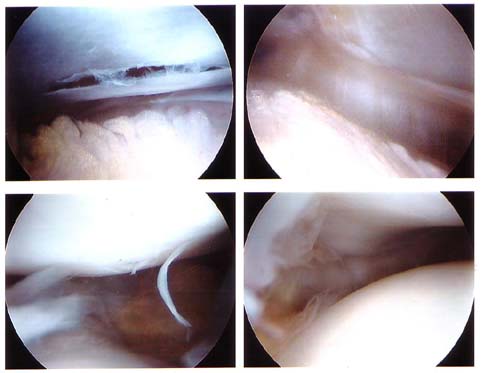

So he went in and this is what he found. The most surprising thing is the upper left picture, which is a “gap” in the tissue of the knee underneath the supra patella pouch. This gap was tethered to several places, perhaps to keep it from separating more. The Dr. thinks these tethers were limiting the patella’s movement, so he trimmed off the tethers and got rid of the gap. He’s fairly optimistic that at least this will help a fair amount. I may still need an LR some day — only time will tell. The other pictures are standard grade 2 chondromalacia, and he cleaned all the loose ends up, etc.